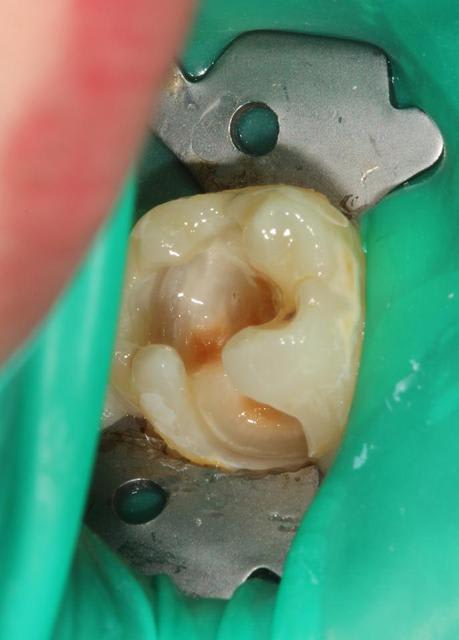

Quelques photos pour illustrer le sujet initial. Dommage que ces dents n'aient jamais eu de sealants.

Pour l'effraction pulpaire sur dent asymptomatique, je fais le protocole que Choixpeau avait mis sur le forum : hypochlorite puis adhésif directement au contact. Aucun problème à court terme pour le moment.

Si effraction plus importante : MTA.